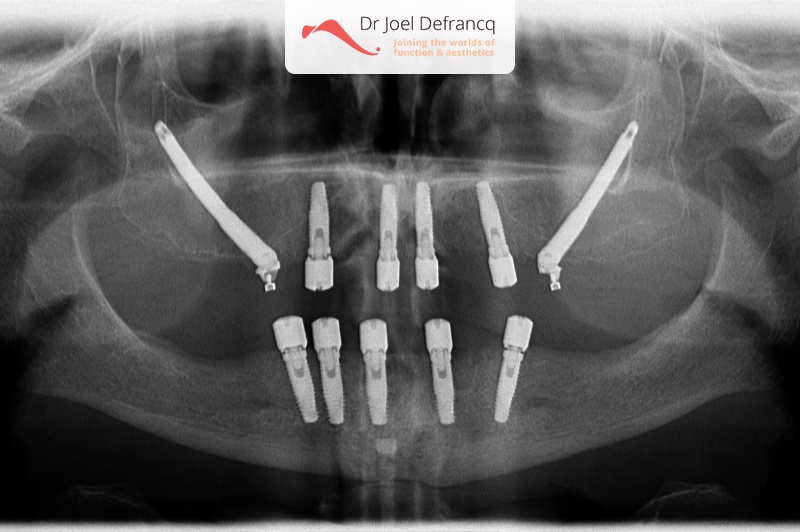

Vita: zygoma implants, all on four.

- Vaste tanden op implantaten (bovenkaak)

- Vaste tanden op implantaten (onderkaak)

- Zygoma implantaten